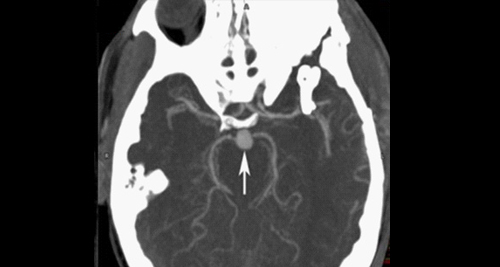

- CT scan: A fast and effective way to detect bleeding in the brain. CT angiography (CTA) can also visualise the blood vessels.

- Cerebral angiography: Considered the gold standard for confirming aneurysm size and shape. A catheter is inserted through the groin and guided to the brain to inject contrast dye for X-ray imaging.